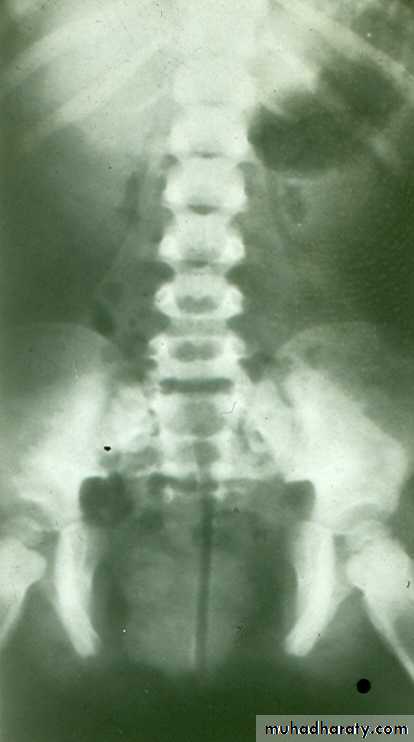

HORSE –SHOE KIDNEY

HORSE SHOE KIDNEY

Fusion of lower pole of both kidneys by bridge of renal tissue (isthmus) crossing in front of aorta, spine and IVC.

IVU shows :

The kidneys at low position .

Close to the spine with long axis parallel to the spine .

Mal–rotation manifested by medially directed calyces.

The renal pelvis and ureters are anterior and lateral in position .

Fusion of upper poles is rare.